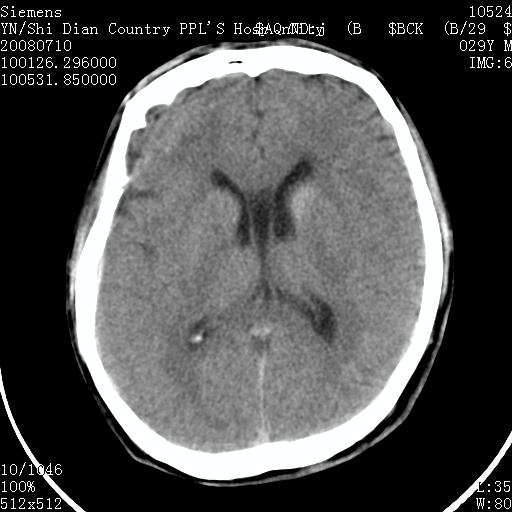

以下是引用随光逐影在2008-7-10 15:19:00的发言:[br]1)考虑左侧尾状核钙化。2)透间隔间腔与vergae腔并存。

以下是引用卜一在2008-7-10 16:43:00的发言:[br]1)考虑左侧尾状核钙化。2)透间隔间腔形成。支持!